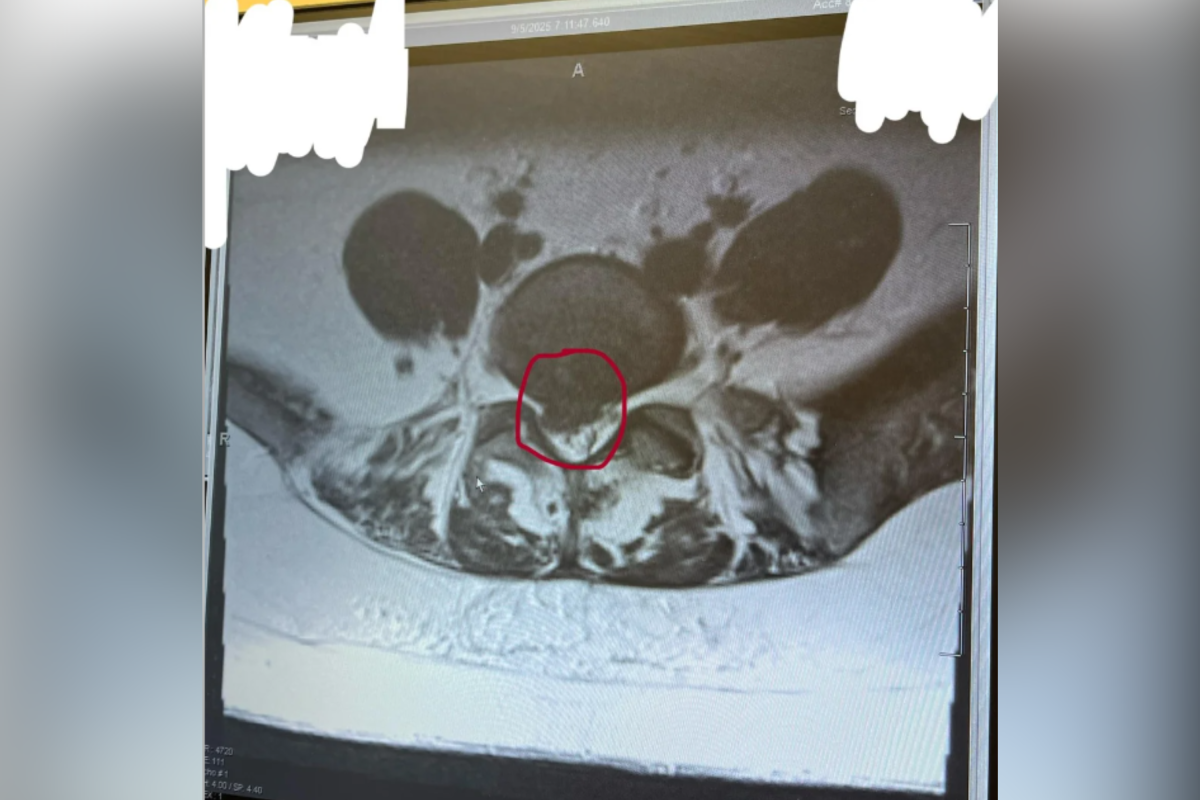

• A doctor diagnosed her with sciatica and later with a herniated disk, also known as a slipped disk.

• Treatment with steroid pills provided temporary relief, but lasting improvement came after the proper diagnosis.

• Shelby has begun treatment, involving steroid injections and plans for physical therapy, but worries about needing surgery in the future.